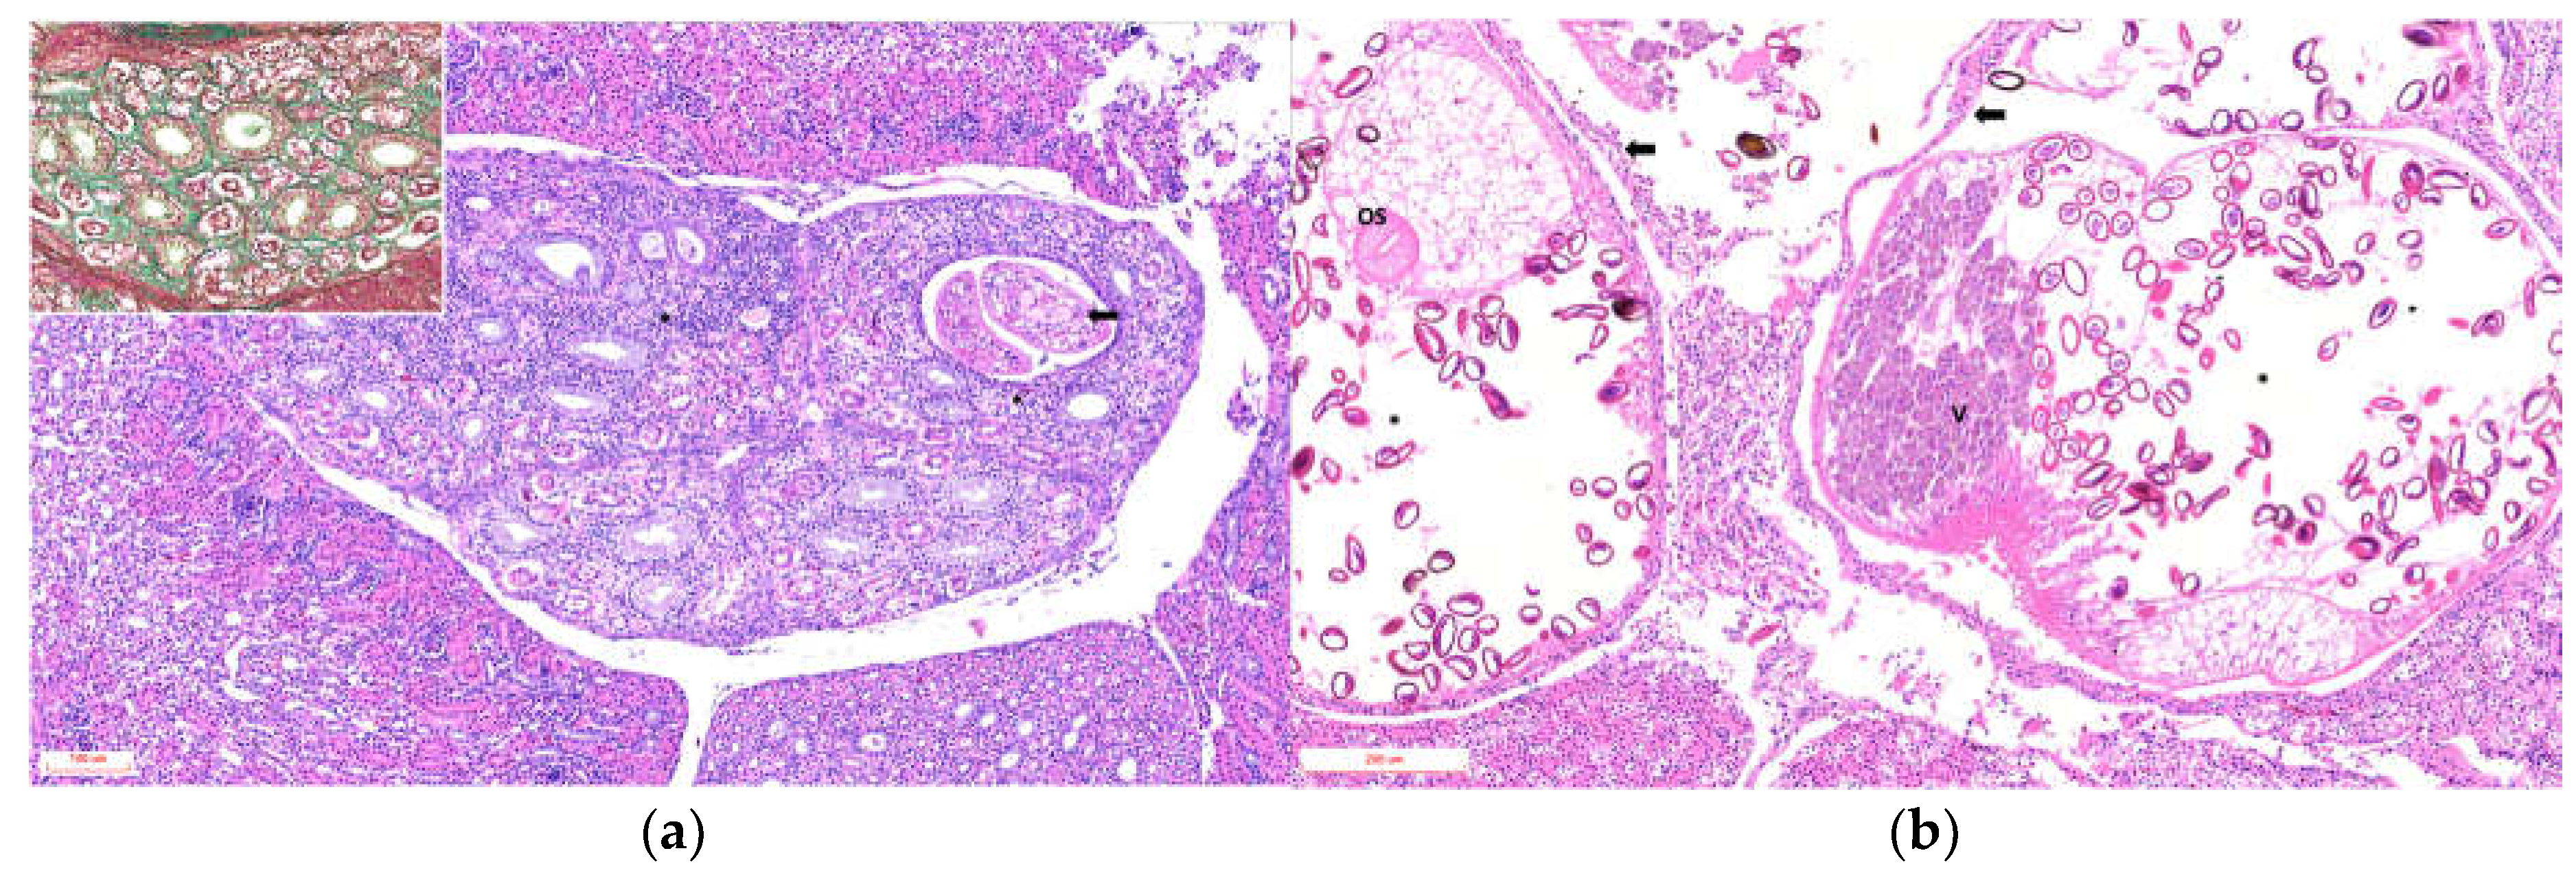

Glomeruli occasionally showed expansion of the urinary space with areas of increased cellularity. The ureters exhibited luminal dilation, epithelial hyperplasia, epithelial cell sloughing, squamous metaplasia, and necrosis, with multiple intraluminal parasitic structures surrounded by abundant macrophages, cellular debris, and heterophils in all cases, varying in severity (Figure 3a). The smooth muscle tissue adjacent to the ureters showed variable damage, mainly degenerative and necrotic lesions of muscle fibers, with moderate mononuclear inflammation on a pale proteinaceous background and edema (Figure 3b).

Figure 3. Photomicrographs of ureters from a Humboldt penguin with severe damage (Animal ID 2) affected by trematodes. (a) Dilated ureter measuring 1,353 × 854 µm with epithelial wall showing areas of degeneration and necrosis. A trematode is present in the lumen, surrounded by abundant macrophages, cellular debris, heterophils, and granular eosinophilic material. VS: ventral sucker; OS: oral sucker; V: vitellaria. (b) Smooth muscle tissue with hyper-eosinophilic, fragmented, and necrotic fibers infiltrated by lymphocytes, plasma cells, and heterophils.